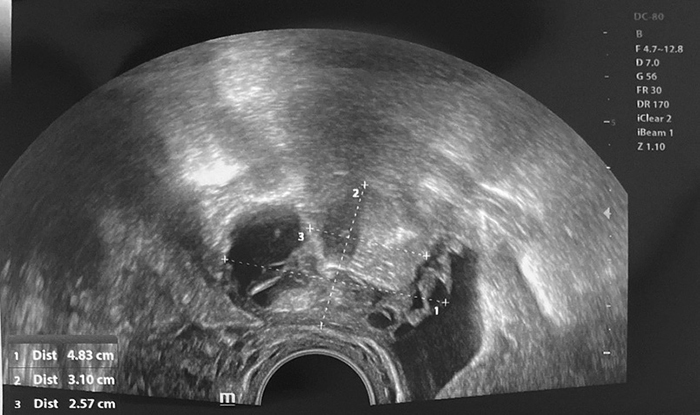

A 25-year-old nulliparous woman with regular menstrual periods consulted a gynecologist because of pain in the left lower abdomen, especially when inserting a menstrual cup or tampon. This pain had persisted for a year. She had no vaginal discharge, fever, dysuria, frequent urination, or diarrhea. Additionally, this woman was consulted by an endocrinologist and a dermatologist for hair loss. Testosterone level was elevated, and she was taking spironolactone for six months. CA125 level and other laboratory values were normal. Transvaginal ultrasound showed larger bilateral ovaries, left ovary enlarged to 4.5x2.5 cm with multiple cysts 2–3 cm in size with echo positive inserts, and right ovary also enlarged to 6.9x4.0 cm with cyst 4.0x3.8 cm in size filled with opaque content (Figure 1, 2).

Figure 1. Right ovary

A pelvic MRI showed three dermoid cysts on the right ovary, the largest of which was 3.2 cm. The left ovary also showed five dermoid cysts, the largest 4.2 cm diameter. A bilateral laparoscopic ovarian cystectomy was performed. During the operation, dermoid cysts containing hair and fat were found in both ovaries. With the help of bipolar coagulator and forceps, three right ovarian dermoid cysts and five left ovarian dermoid cysts were enucleated. To preserve the largest possible ovarian reserve, the ovaries were minimally coagulated and sutured to ensure hemostasis. Histopathological findings confirmed mature benign teratomas on both sides with no immature tissue. These non-malignant tumors had multi-layered squamous epithelium, mature adipose, and nervous tissue with inclusions of keratin masses. After 6 and 12 months, the patient came for a follow-up checkup. At both time points, ultrasound showed that the bilateral ovaries were normal in size with sufficient reserve (the antral follicle count was 6 to 8 in both ovaries). Still, a minor about 10 mm hyperechogenic mass in the right ovary (without positive growth dynamic) was a probable sign of recurrent dermoid cyst.